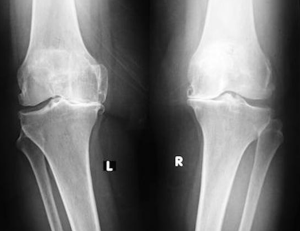

Artroz için en önemli risk faktörü yaştır. 65 yaşın üzerindeki kişilerin üçte birinde röntgen grafileri ile saptanan artroz bulguları vardır. Obezite en önemli faktörlerden birisidir. Yaştan bağımsız olarak obez kişilerde artroz riski erkeklerde 2 misli, kadınlarda 3 misli artar. Bilinmeyen nedenlerden dolayı kadınlarda artroz erkeklere oranla iki misli daha sık görülür. Ailevi birtakım faktörlerin de olduğu düşünülmektedir.

Artrozun tanısı oldukça kolaydır. Doktorunuz size bazı sorular sorduktan sonra muayene eder. Bu sırada, geçirilmiş olan kaza, yaralanma ve ameliyatlarınızı mutlaka doktorunuza bildirmeniz gerekir. Çoğu zaman basit bir röntgen grafisi ile tanı konabilir. Erken artroz durumlarında röntgen grafileri normal olabilir, bu durumda MRG (manyetik rezonans görüntüleme) yararlı olabilir. Artrozda genellikle kan testleri normaldir, ancak başka hastalıkları ayırd edilmesi için kan testleri gerekli olabilir.